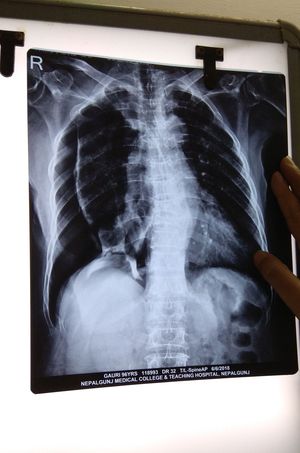

Haemothorax or pneumothorax i think

Rt peumothorax with ribs fracture ,difficult to comment on left bcoz poor quality of xray

Spinal fracture as well? Mild scoliosis? Please explain